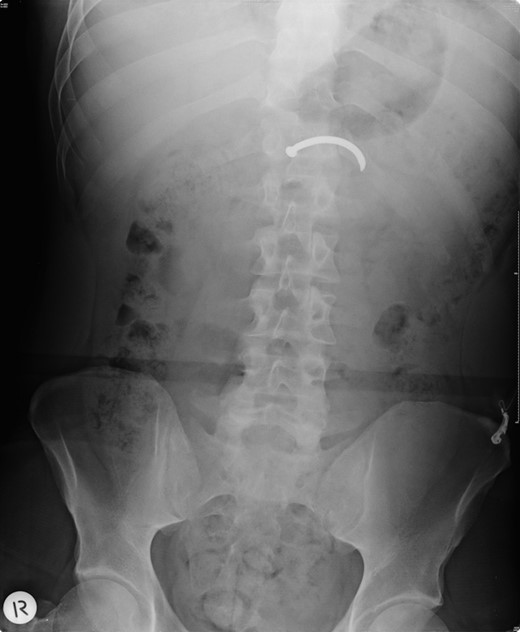

The patient arrived in the emergency department of The Alfred Hospital 25 min after the accident. A FAST scan (Focused Assessment with Sonography for Trauma) was positive. A plain abdominal radiograph confirmed the presence of a single nail in the abdomen. A subsequent CT scan showed that the nail was positioned within the transverse colon with free air and fluid surrounding the liver, spleen and paracolic gutters, and a perforation of the horizontal duodenum with retroperitoneal free air and fluid. No vascular injury was seen (Figs 1 and 2).

Plain abdominal radiograph showing the position of a single nail in the abdomen.